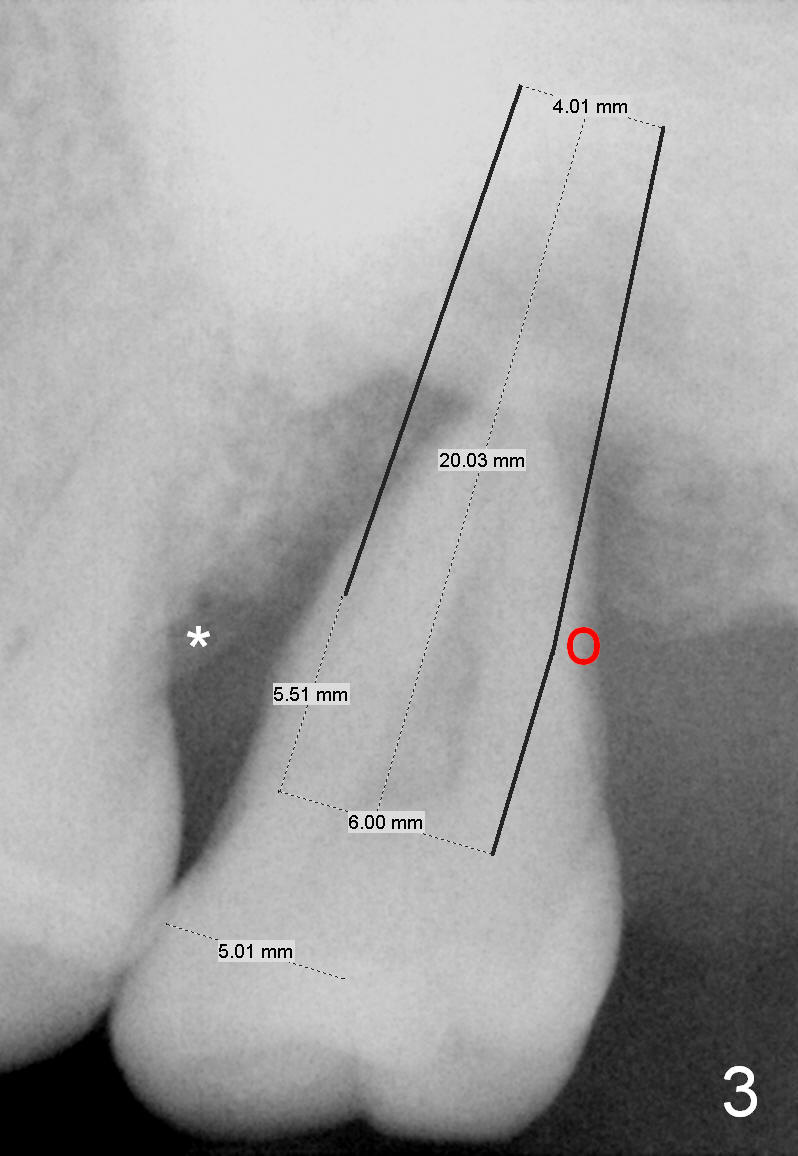

A 49-year-old lady has history of periodontal disease (Fig.1). The teeth #2 and 19 have been extracted and replaced by immediate implants. When she returns, crown is going to be cemented at #19 and delayed implant will be placed at #15. The tooth was extracted 4.5 years ago. No PA has been taken since extraction. Fig.2,3 show design for immediate implant if the tooth were not extracted (*: mesial crest; O: bone graft). Note the orientation of the implant and the space from the neighboring tooth.